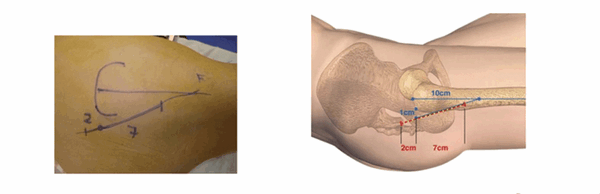

Нанесение маркеров для выполнения разреза. (Graphique de l’incision)

Нанесение ориентиров упрощает выполнение разреза. Верхний бугор большого вертела хорошо пальпируется, когда пациент находится в положении лежа на боку на плоской поверхности. От этого места наносятся две точки: первая на расстоянии 1 см располагается за бугром большого вертела, вторая — на расстоянии 10 см от вершины по оси бедренной кости. По линии, связывающей эти две точки делается разрез: 2 см ниже и 7 см выше от бугра вертела.

Схема выполнения модифицированного бокового доступа к тазобедренному суставу пациентки Л.: на средней ягодичной мышце намечены три разреза для формирования лоскута (интраоперационное фото)